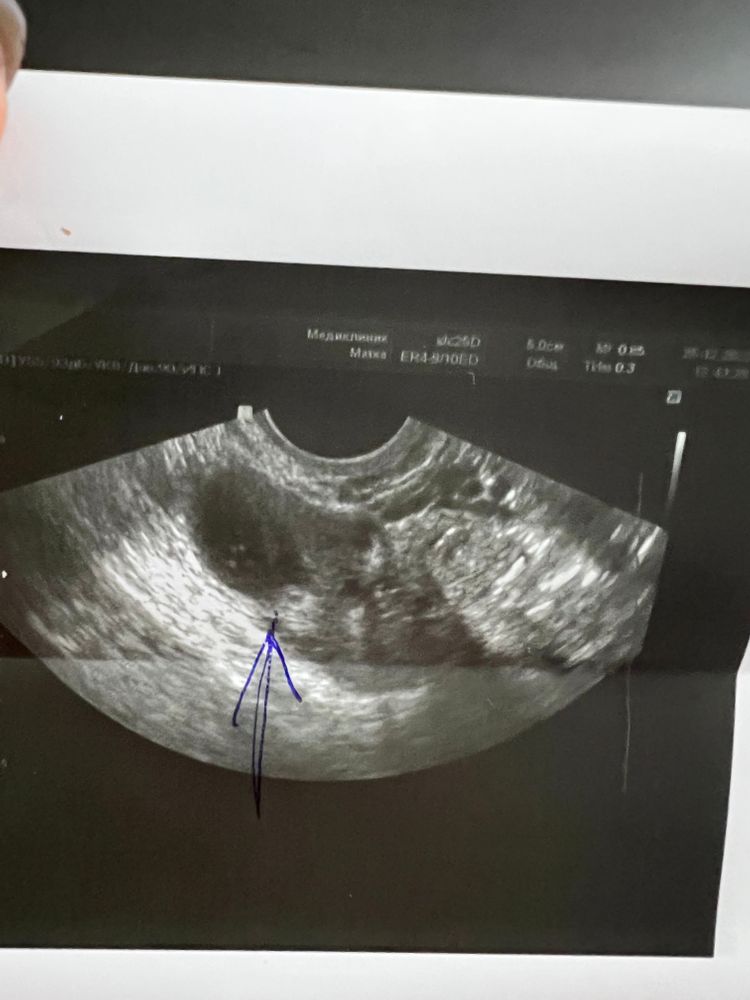

Желтое тело где?((

А смысл делать сто узи?вам же врач сказал ,что есть?вот это темное пятно оно и есть,жт почти как большой фолликул на узи выглядит,образование на яичнике.его еще смотрят через световой режим,оно подсвечивается желтеньким.

Елена Л, ну ладно, просто в прошлый цикл оно как с картинки прям было, а в этот раз ну пятно и пятно 🙄 на дф похоже

Катерина, да да,именно очень похоже на дф,они даже проверяют узисты иногда вот этим световым эффектом,не знаю как правильно называется.